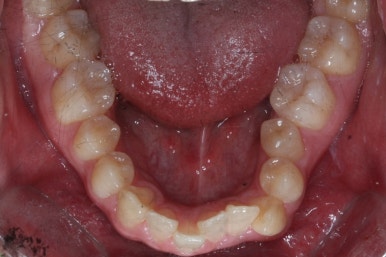

부산구순구개열 키다리아저씨치과에 처음 오셨을 때의 입 안의 모습입니다.

입천장이 갈라져서 어릴 때 봉합 수술을 했기 때문에 그 상처가 굵게 남아있는 것을 볼 수 있습니다. 일반적으로 피부상처도 다른 부위보다 단단하듯이 입천장의 봉합 상처도 매우 단단하게 아물기 때문에 성장에 방해를 주게 됩니다.

가로폭이 매우 좁고 찌그러져 있습니다.

또한 위턱이 앞으로 자라나는 것도 방해해 대부분 앞니가 거꾸로 물리게 됩니다.

또한 가랄져 있던 선에 걸쳐 있는 영구치 일부는 선천결손이 되는 경우가 많습니다.

이번 환자분도 이런 특징을 모두 갖고 계셨습니다.

악궁확장이 시작될 시점과 악궁확장을 다 진행했을 시점의 비교입니다.

확실히 좁아져 있던 가로 넓이가 넓어진 것을 볼 수 있습니다.